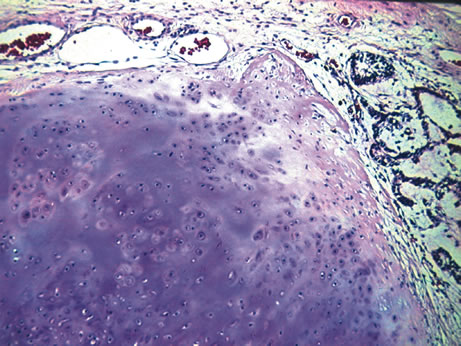

Fuchs' adenoma (pseudoadenomatous hyperplasia) rarely becomes evident clinically but may appear as a glistening, white irregular tumor arising from the ciliary body.85,86 It consists of a benign proliferation of nonpigmented ciliary epithelial cells with accumulation of basement membrane-like material (Fig. 15).

Fig. 14. Teratoid medulloepithelioma. The tumor shows cartilage and foci of medullary epithelial cords at the periphery. (Hemotoxylin-eosin ×60.)

Fig. 15. Fuchs adenoma. Histologically, pseudoadenomatous hyperplasia of the nonpigmented ciliary epithelium is noted. (Hemotoxylin-eosin ×15.)